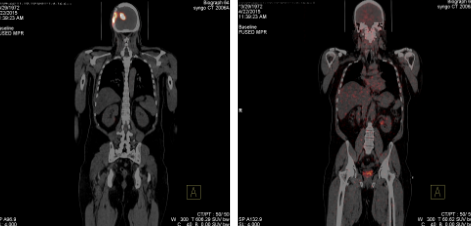

Alpha therapy is clearly more effective to standard therapy with or without Avastin (todays protocol)

| RX-TMZ-placebo* | RX-TMZ-avastin* | |||

|---|---|---|---|---|

| > 24 m (2 years) | 9/20 (45%) | 4/10 (40%) | 118/463 (26%) | 139/458 (30%) |

| > 30 m (2 1/2 years) | 6/20 (30%) | 4/10 (40%) | 53/463 (11%) | 61/458 (13%) |

| > 36 m (3 years) | 4/20 (20%) | 2/10 (20%) | 15/463 (3%) | 11/458 (2%) |

| > 42 m (3 1/2 years) | 3/20 (15%) | 2/10 (20%) | None | 1/458 (0.2%) |

| > 48 m (4 years) | None | 1/10 (10%) | None | None |